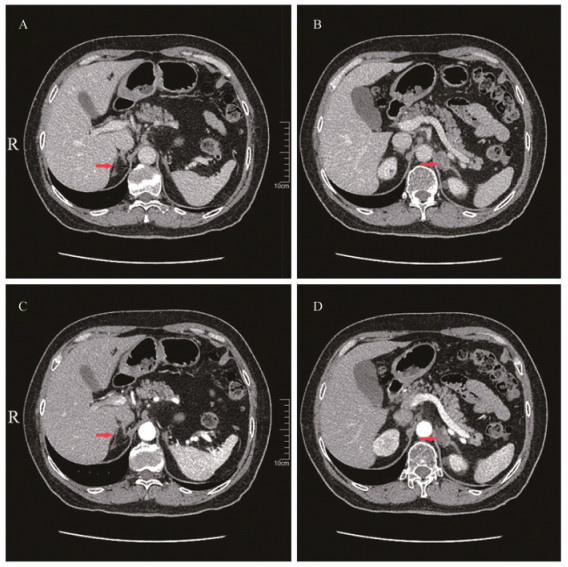

Fig 1 Adrenal characteristics of the patient A and B: Non-contrast CT; C and D: Contrast-enhanced CT. A mass was observed in the left adrenal gland, suggestive of an adenoma, measuring approximately 24 mm×16 mm. The unenhanced CT attenuation value was 19 HU(the arrow in B), and the post-contrast CTattenuation values in 3 phases were approximately 35, 55 and 31 HU(the arrow in D). No abnormalities were observed in the right adrenal gland(the arrow in A and C).